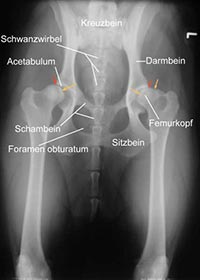

Hüftgelenksdysplasie HundDie Ausprägung klinischer Symptome einer HD variiert in Abhängigkeit vom Alter bzw. Stadium der Krankheit. Bei relativ jungen Tieren, im Alter von einem halben bis einem Jahr, kommt es zur Schmerzhaftigkeit, weil der Oberschenkelkopf in der Hüftgelenkspfanne (Acetabulum) nur ungenügenden Halt findet und durch seine abnorme Beweglichkeit schmerzregistrierende Nervenfasern der Knochenhaut des Pfannenrandes gereizt werden. Ältere Tiere bilden Schmerzhaftigkeiten eher infolge fortschreitender degenerativer Veränderungen (Arthrosen) des Hüftgelenkes aus.

Eine zuverlässige Möglichkeit zum Erkennen des Schweregrades der Erkrankung bildet die Röntgenuntersuchung. Da bei dieser die Gelenke überstreckt werden müssen, was beim Vorliegen einer HD starke Schmerzen verursacht, wird sie unter einer Kurznarkose durchgeführt. Voraussetzung für eine aussagekräftige Diagnose ist die exakte Positionierung des untersuchten Tieres in Rückenlage mit gestreckten, parallel gelagerten Oberschenkeln und orthograd zum Strahlengang eingedrehten Kniescheiben.

Morgan LinieWeitere Kriterien zur Beurteilung sind die Kongruenz von Oberschenkelkopf und Gelenkpfanne, die Weite des Gelenkspaltes, die Pfannenkontur, die Kontur des Oberschenkelkopfes sowie das Vorhandensein von Hinweisen auf arthrotische Prozesse wie walzenförmige Verdickungen des Oberschenkelhalses, Randwülste an der Gelenkpfanne, unter dem Knorpel befindliche Verdichtungen der Knochensubstanz im Pfannenbereich und die Einlagerung von Knochenmaterial am Ansatz der Gelenkkapsel (Morgan-Linie).